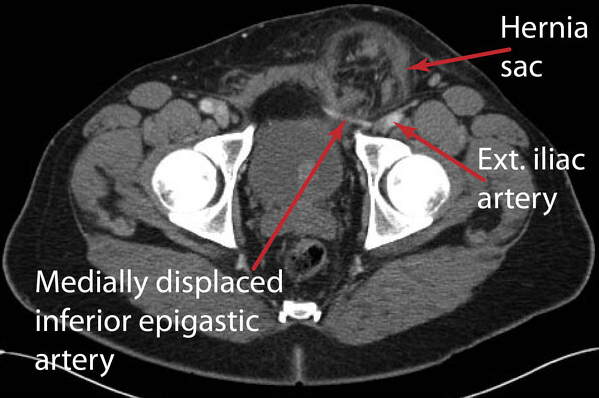

(2) CT: Pelvic bone 바깥으로 탈장이 발생한 모습

• Inferior epigastric vessel 외측에 탈장이 있으면 간접 샅굴탈장, 내측에 탈장이 있으면 직접 샅굴탈장이다 (사진 참조).

간접 샅굴탈장 환자의 복부 CT